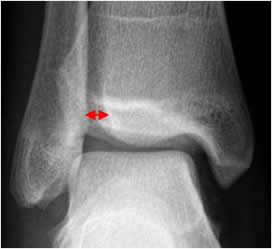

Sindesmosis tibioperonea:

En lesiones de la sindesmosis tibioperoneoastragalina, se produce ruptura de los ligamentos tibioperoneo anterior y posterior. En la Rx AP existe aumento del espacio entre la tibia y el peroné mayor de 6 mm. (29). (Fig 87 y 89).

Fig 87. Espacio tibioperoneo.

Rx AP. Espacio normal entre la tibia y el peroné.

Sombra tibioperonea:

El maleolo tibial lateral se superpone al peroné, entre 8 y 10 mm. (3). (Fig 88). Este espacio también disminuye, en la diastasis tibioperonea. (3). (Fig 89.).

Fig 88. Sombra tibioperonea.

Rx AP. Interposición normal del maleolo, sobre el peroné.

Fig 89. Lesión de ligamentos de la mortaja tibioperonea.

A: Rx AP. Aumento del espacio tibioperoneo y disminución de la sombra tibioperonea, lo que hace sospechar lesión ligamentaria.

B: TAC axial. Aumento del espacio tibioperoneo posterior, por lesión ligamentaria.